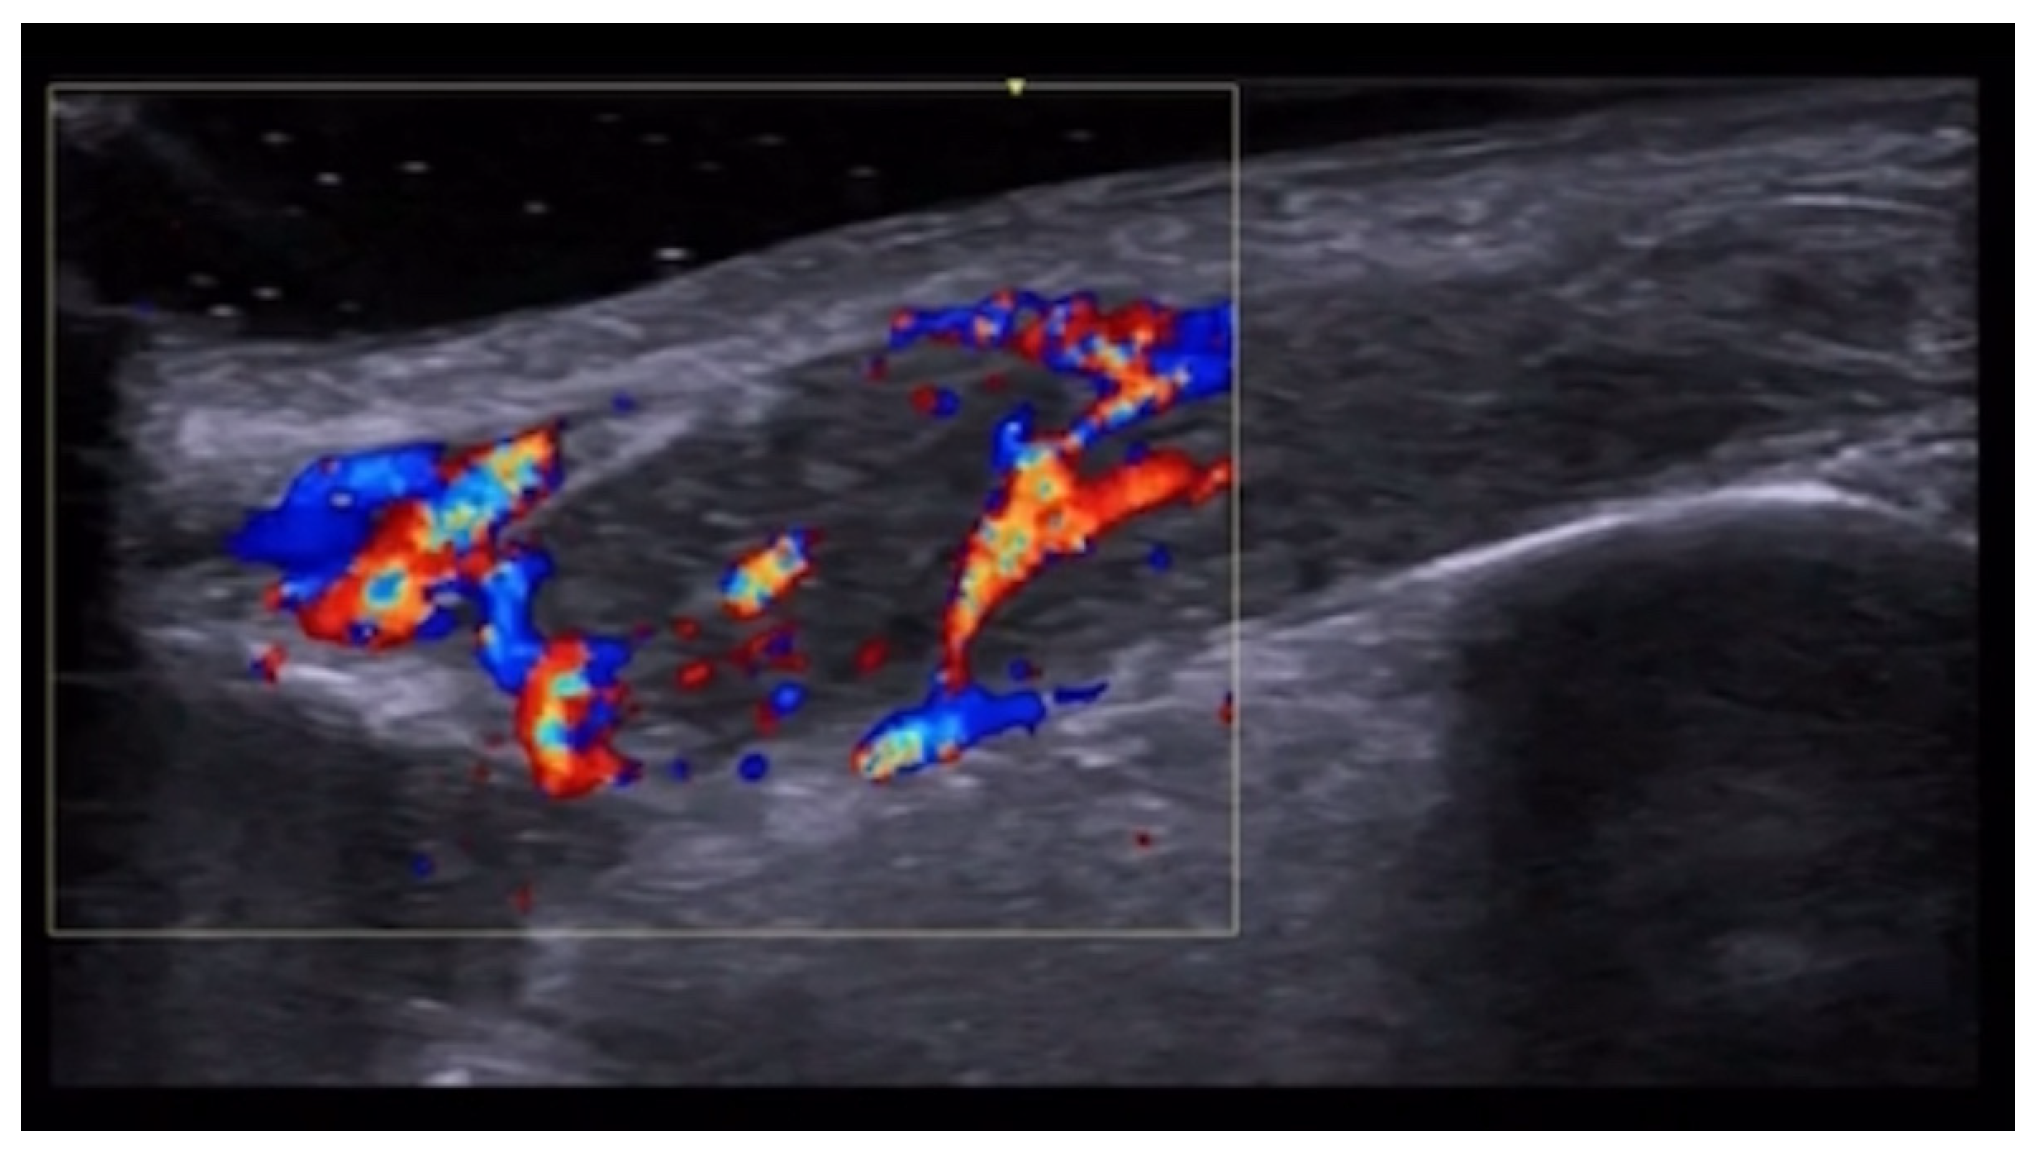

- Rodríguez Bandera, A.I.; Feito Rodríguez, M.; Chiloeches Fernández, C.; Stewart, N.; Valdivielso-Ramos, M. Role of colour-Doppler high-frequency ultrasonography in capillary malformation-arteriovenous malformation syndrome: A case series. Australas. J. Dermatol. 2020, 61, 349–352. [Google Scholar] [CrossRef] [PubMed]

- Velthuis, P.J.; Jansen, O.; Schelke, L.W.; Moon, H.J.; Kadouch, J.; Ascher, B.; Cotofana, S. A Guide to Doppler Ultrasound Analysis of the Face in Cosmetic Medicine. Part 1: Standard Positions. Aesthetic Surg. J. 2021, 41, NP1621–NP1632. [Google Scholar] [CrossRef]

- Vasconcelos-Berg, R.; Izidoro, J.F.; Wenz, F.; Müller, A.; Navarini, A.A.; Sigrist, R.M.S. Doppler Ultrasound-Guided Filler Injections: Useful Tips to Integrate Ultrasound in Daily Practice. Aesthetic Surg. J. 2023, 43, 773–783. [Google Scholar] [CrossRef]